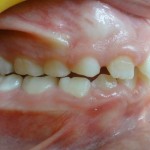

Elle est utilisée lorsque les dents du haut sont trop en avant des dents du bas. C’est un appareil orthopédique, c’est-à-dire qu’il n’agit pas sur les dents mais qu’il a un effet au niveau du squelette.

Vue de Droite